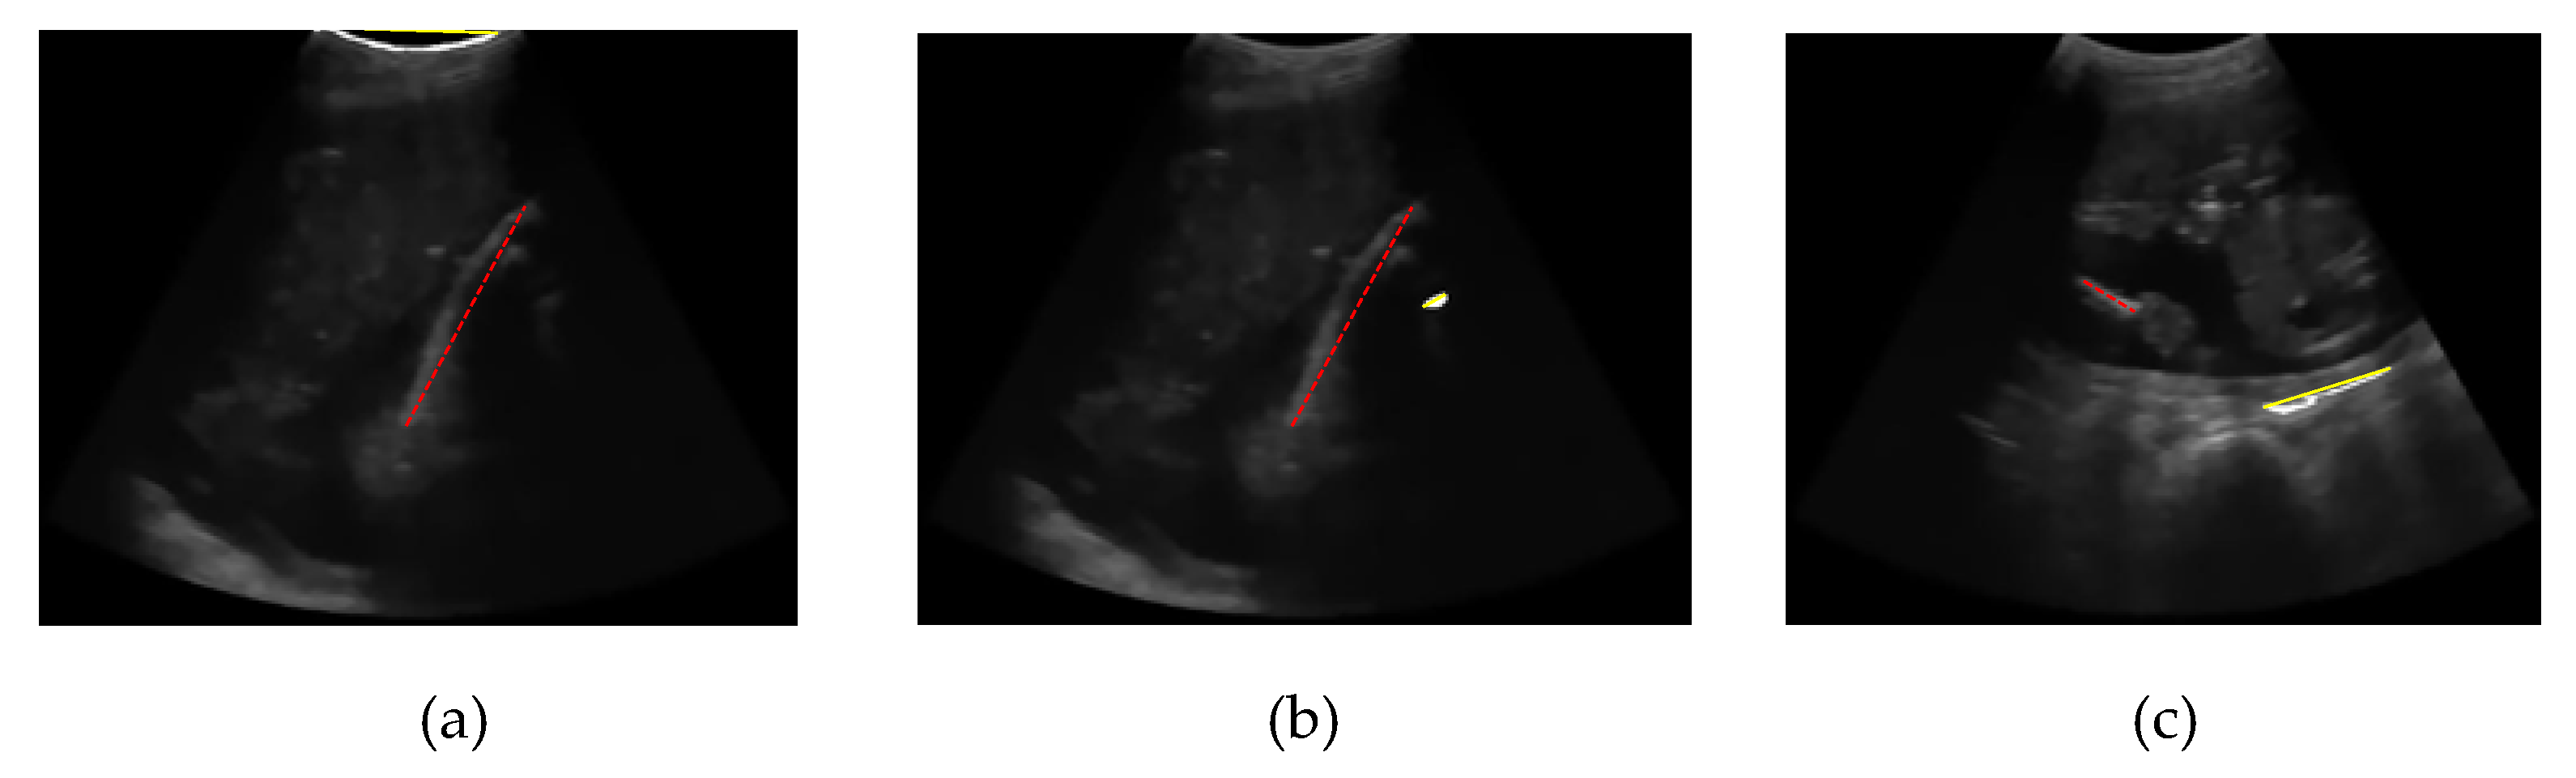

Some femur detection failures of other methods are shown in Figure 22. Failure of the entropy method occurs because the threshold result is only a few pixels and is in the upper boundary area of the image. Thus, the point is detected as the starting point of the segmentation of the femur object, as shown in Figure 22(a). The error of the Otsu multilevel method, as shown in Figure 22(b), is due to the broader thresholding results from the top to the lower end. Therefore, at the object selection stage, the area was discarded because the femur was not indicated, and the object of the femur was a smaller object. In statistical-based methods, femur errors occur at a gestational age of approximately 15 weeks, when the size of the femur is small, and an ultrasound probe still exposes the foetal sac. The outer area of the sac had an intensity value higher than that of the femur bone, so that the region was recognised as a femur object, as shown in Figure 22(c).

Figure 22. Failures result of (a) entropy-based method, (b) multilevel Otsu method, (c) statistical-based method, where the dash line is the ground truth, and the straight line is a detected FL.